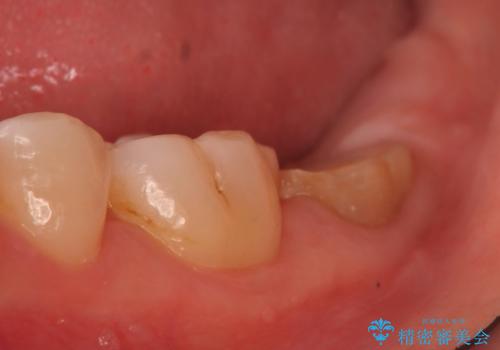

深い虫歯により抜歯となった奥歯 インプラント治療でかみ合わせを回復する

- 治療計画

- 保存不可能な歯の抜歯後、待時にてインプラントを埋入、2回法にて咬合回復を計画した。

同時に、前後の歯の金属のやり直しも行った。